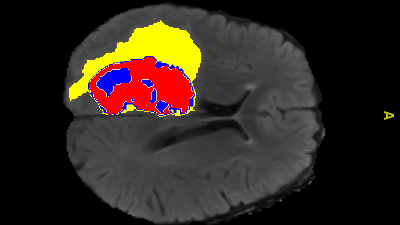

AI-annotated medical image showing enhanced tumour, tumour core and edema regions. Image credit: Monash University